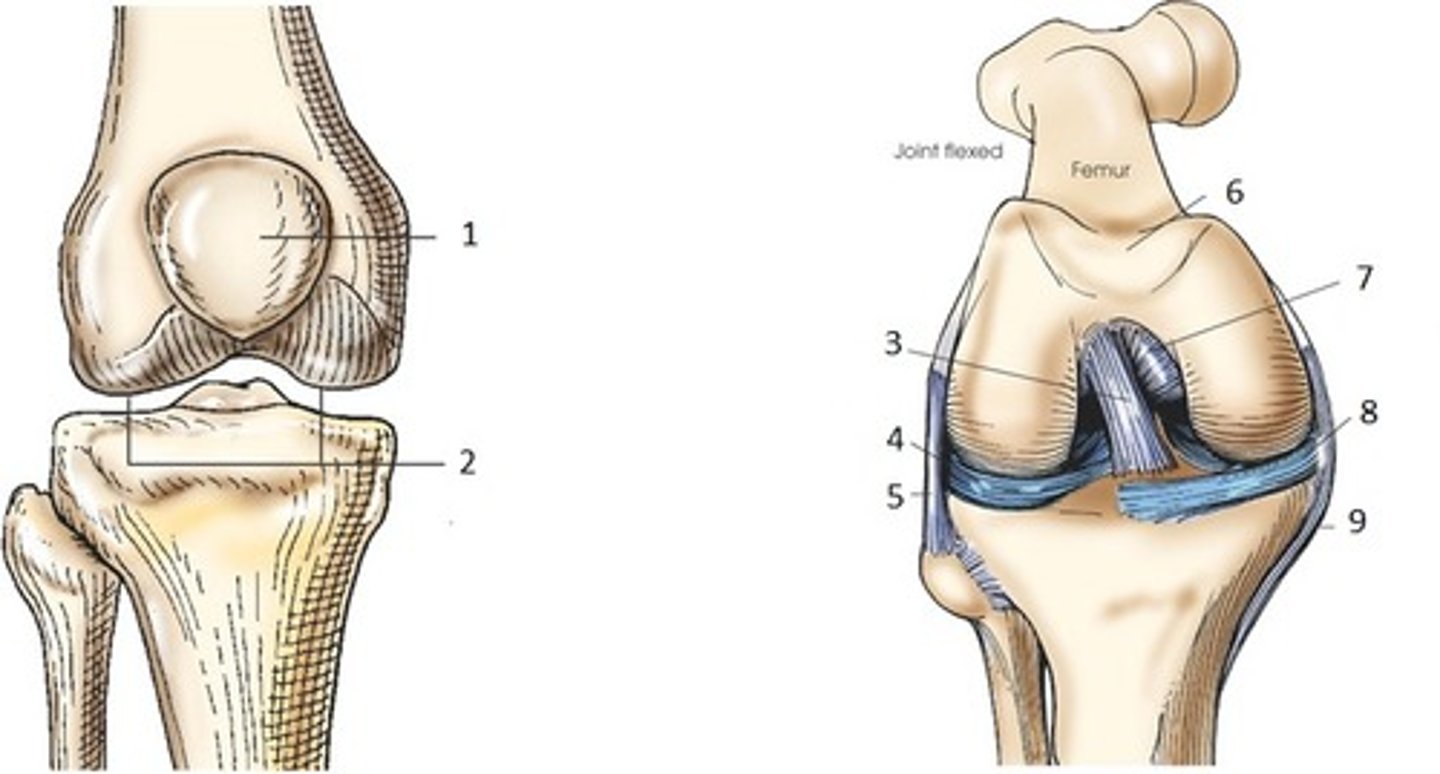

Bicondylar synovial joint

allow movement mostly in one axis with limited rotation around a second axis

-formed by two convex condyles that articulate with concave or flat surfaces

ex: knee joint